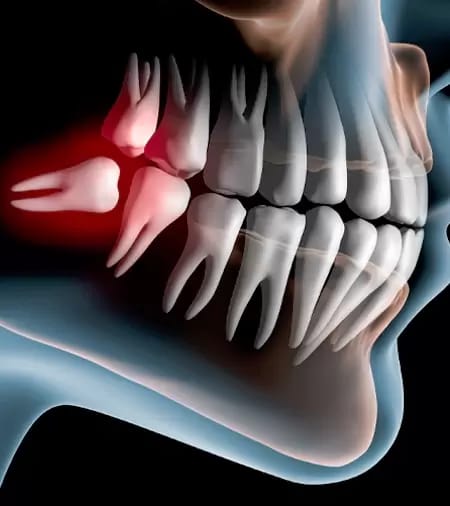

Surgical Extractions & Wisdom Teeth Extraction

Surgical extractions are done for teeth that are broken, impacted, or difficult to remove safely. Wisdom teeth extraction helps prevent pain, swelling, and future dental problems caused by crowded or misaligned wisdom teeth